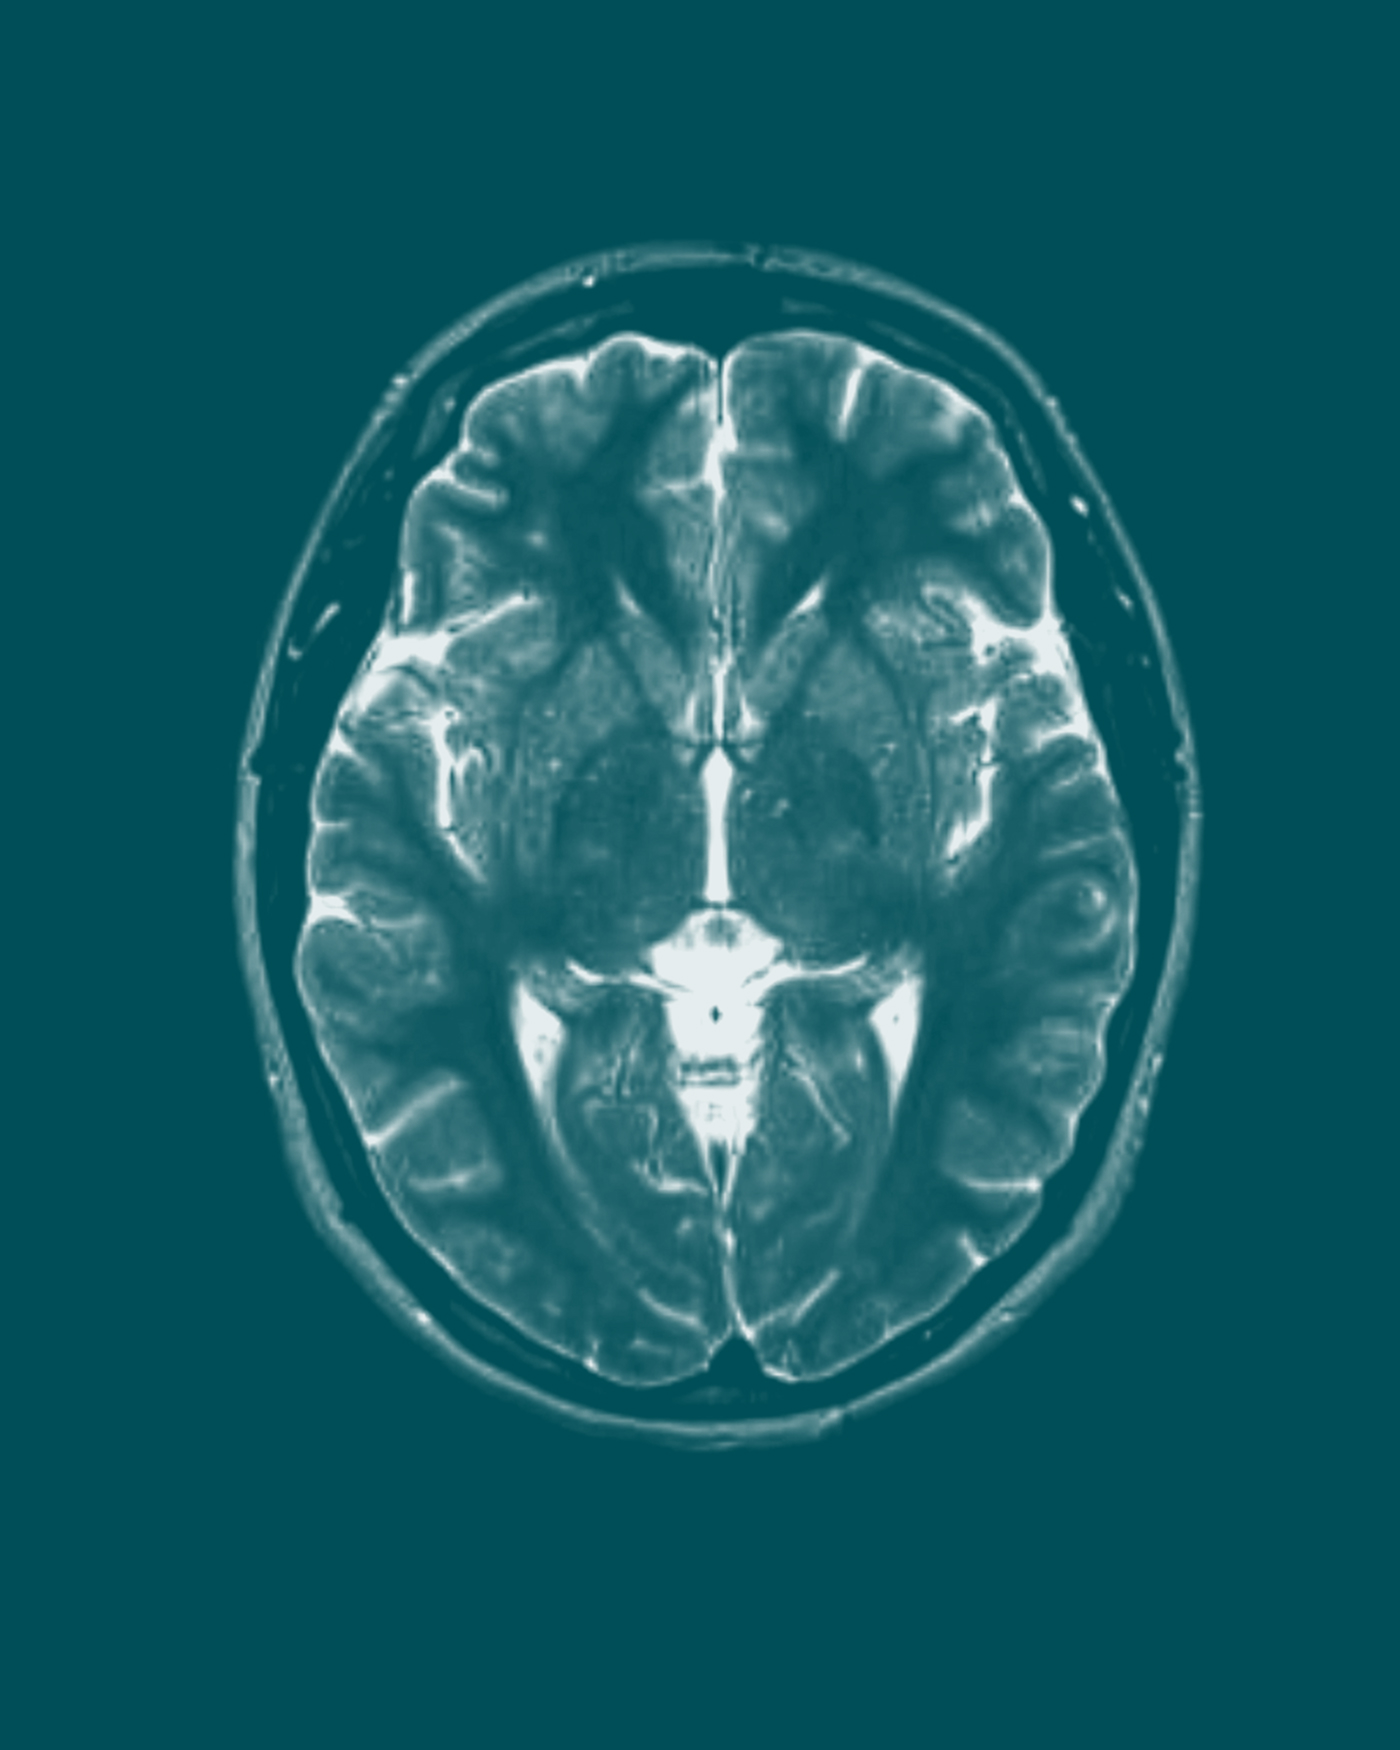

Commonly used by women seeking a long-term, reversible contraceptive method, Depo-Provera is highly effective, with a success rate of over 99% when used correctly. However, it is associated with various known side effects, such as weight gain, mood changes, decreased bone density, and menstrual irregularities. Based upon research published in March 2024, users of Depo-Provera face a 5.6 times greater chance of developing meningiomas, a form of brain tumor, than those who do not use Depo-Provera. Despite this, the makers of Depo-Provera do not warn women about this risk.